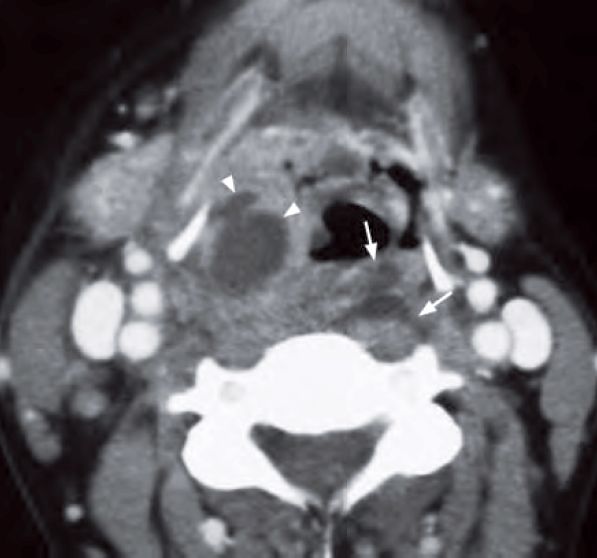

A contrast enhanced CT neck was performed (image below) which showed:

- Prominent retropharyngeal soft tissues

- Large rim-enhancing lesions with necrotic centre in retropharyngeal soft tissue consistent with an abscess